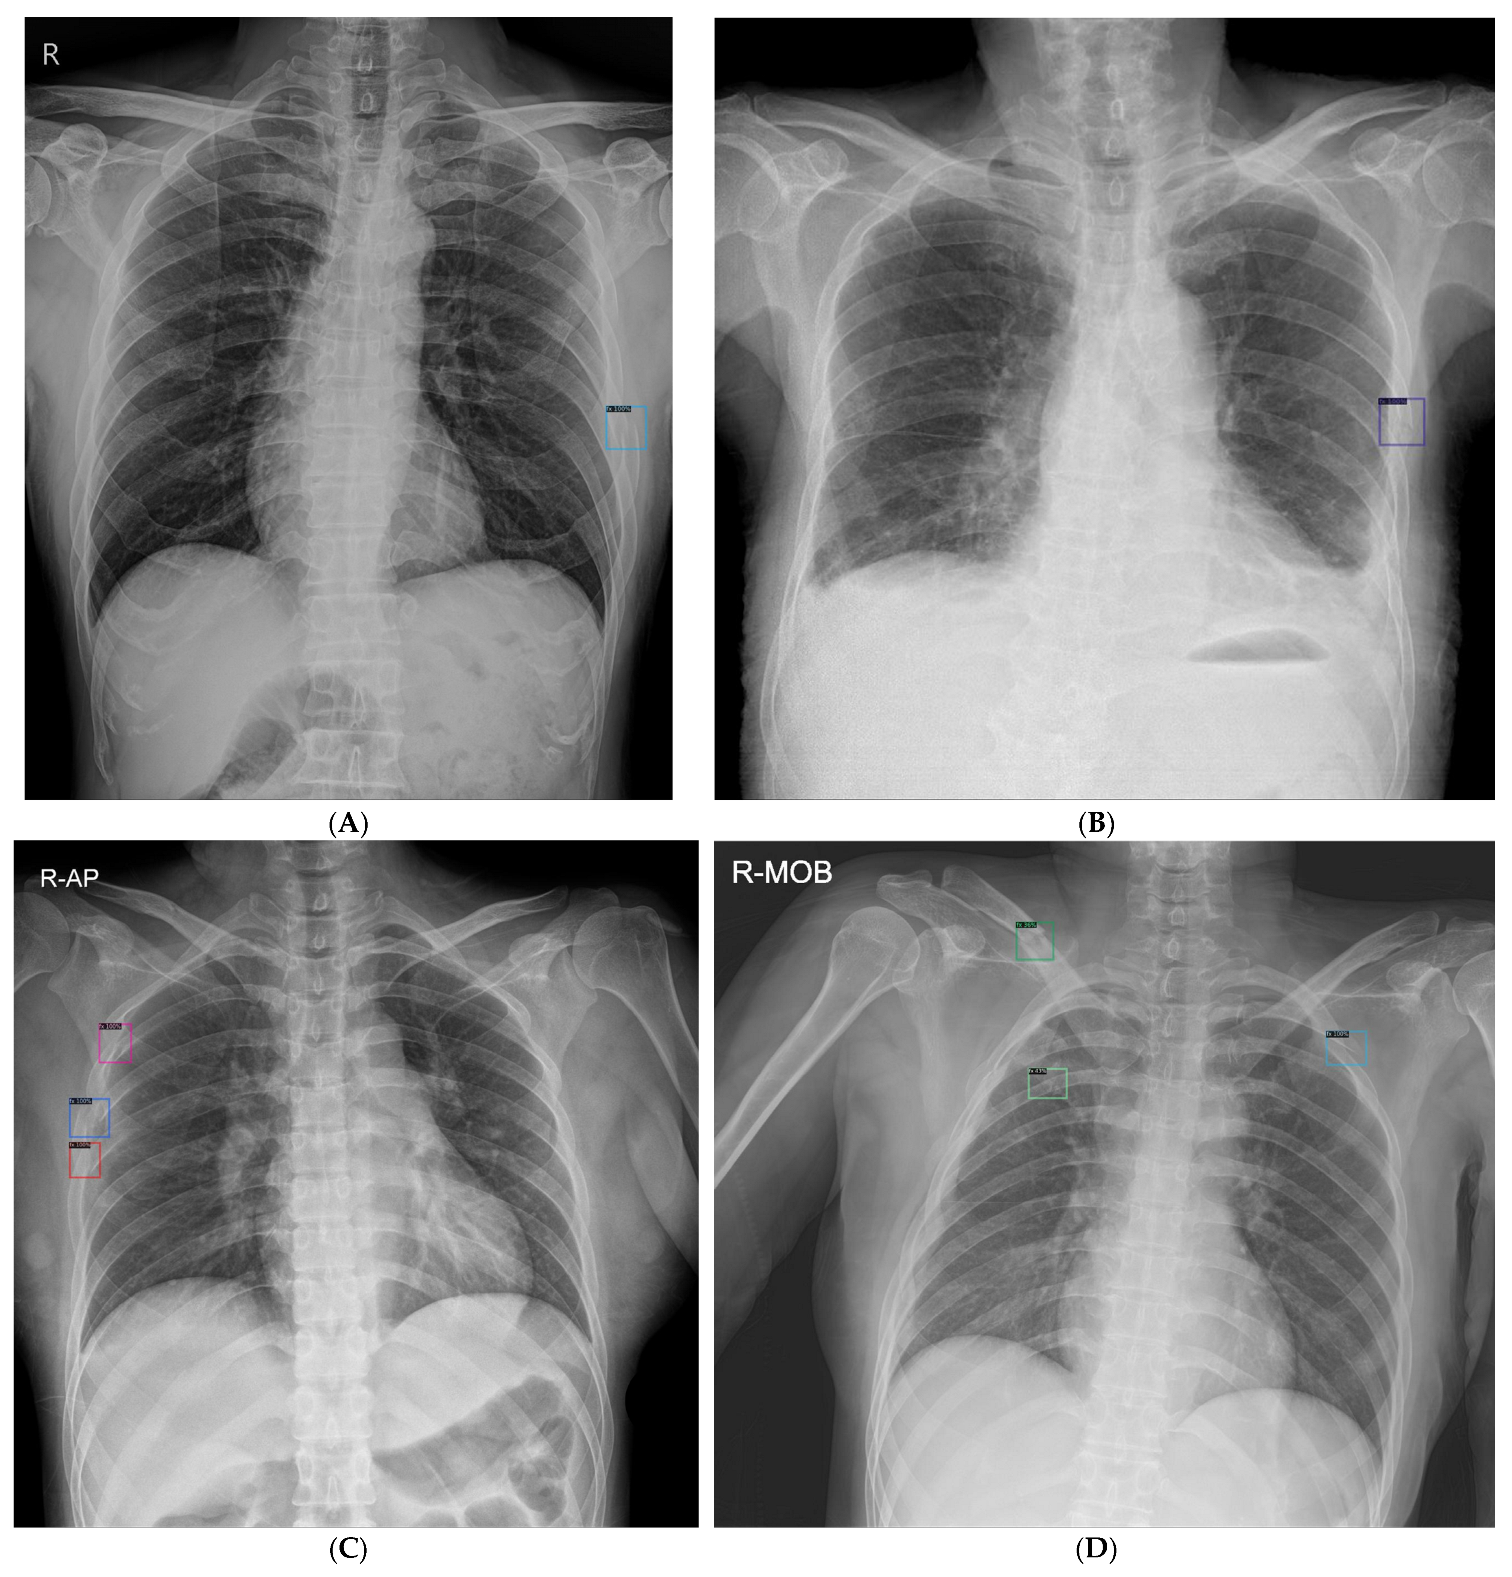

2.2. Rib Fracture Annotation on Chest Radiographs